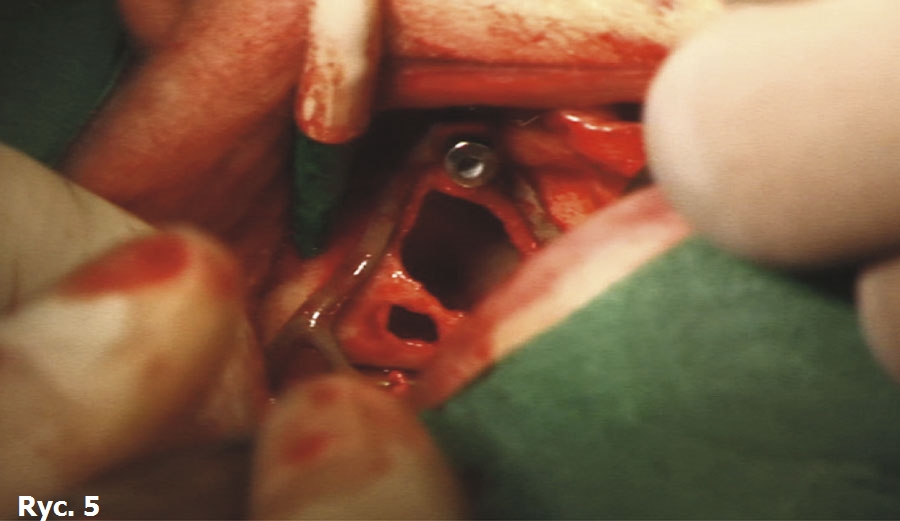

Pacjentka wyraża zgodę na zabieg chirurgiczny, polegający na wprowadzeniu wszczepów podokostnowych, zdając sobie sprawę, że jest to ostatnia deska ratunku, umożliwiająca stabilne zakotwiczenie protezy wspartej na wszczepach. Po zabiegu implantacji dwie oddzielne siatki podokostnowe (ryc. 3) zostaną ze sobą połączone (ryc. 4). Podniesiony płat śluzówkowo okostnowy (ryc. 5) ukazuje zgodność anatomii tkanki kostnej z modelem stereolitograficznym. Pozabiegowe zdjęcie pantomograficzne (ryc. 6) obrazuje idealne połączenie między dwiema siatkami, umieszczonymi precyzyjnie na swoim miejscu. Mezostruktura (ryc. 7) jest odpowiednim podparciem dla docelowej protezy typu „U” (ryc. 8).